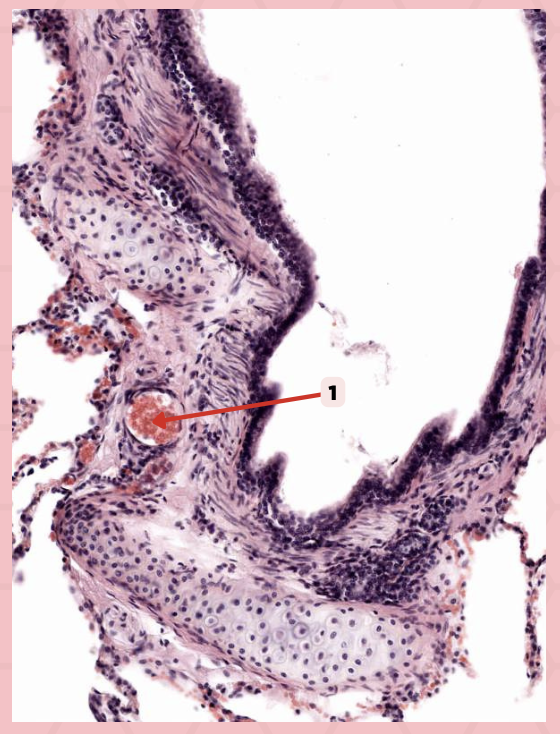

Type 1 and Type 2 Alveolar Cells

What are the 2 cell types for alveoli?

Simple squamous epithelium

What kind of epithelium are these alveolar cells?

Interalveolar septum

Identify the structure labeled as 1.

Type I alveolar cell

Identify the structure labeled as 2.

Type II alveolar cell

Identify the structure labeled as 3.

Pulmonary Alveolar Macrophages (Dust Cells)

Identify the structure labeled as 4.

Pulmonary Alveolar Macrophages (Dust Cells)

What are the most numerous cells inside the alveoli?

Pneumocyte Type I

Which of the following labeled structures covers 95% of the alveolar surface?

Type I alveolar cell

Identify the structure labeled as 1.

Type II alveolar cell

Identify the structure labeled as 2.

Pulmonary Alveolar Macrophages (Dust Cells)

Identify the structure labeled as 3.

Endothelial Cells

Identify the structure labeled as 4.

Visceral Pleura

What type of pleura is a thin layer of connective tissues that borders on the outside by mesothelium?

Simple Squamous Epithelium

What epithelium lines the red arrow?

Mesothelium

Identify the structure labeled as 1.

Pulmonary Capillaries

Oxygenated blood is collected by structure #2 from what source/structure?

Pulmonary Trunk

From what other structure does structure #1 arise from?